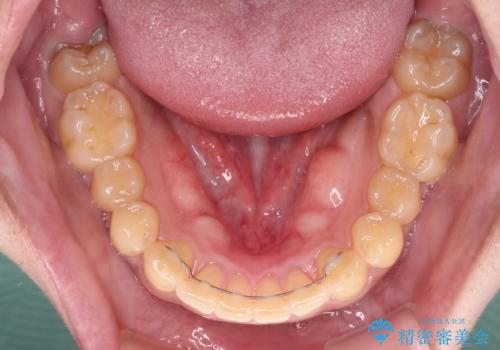

気になる八重歯を抜歯矯正で改善 補助装置を用いたインビザライン矯正

- 上顎の八重歯と前歯のデコボコを気にして来院された患者様です。

八重歯の移動量が多く、インビザライン単体での治療は困難と判断し、補助装置により八重歯移動後にインビザラインを用いることとしました。